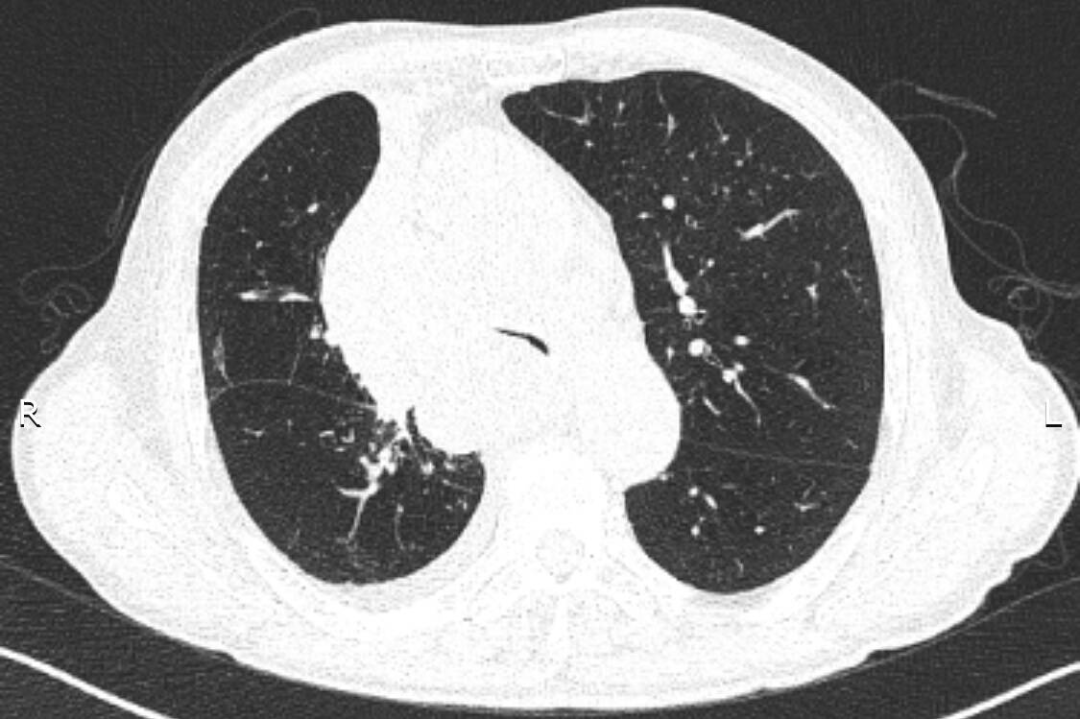

入院后給予吸氧、藥物治療,癥狀緩解不明顯。張強主任結(jié)合患者的癥狀、體征及CT表現(xiàn),考慮憋喘主要為腫瘤浸潤壓迫氣道引起,緊急行電子氣管鏡檢查,明確了氣道被壓迫情況。正常成人氣管內(nèi)鏡約2.5cm,患者氣管下段重度狹窄,直徑僅約3mm,而且狹窄一直延續(xù)到右主支氣管末端,左主支氣管狹窄情況還稍輕些。建議患者可緊急置入支氣管支架短期緩解癥狀,綜合支架特點、支架定制周期、患者病情、費用等情況后,家屬希望能為患者盡快放置硅酮支架。張強主任立即聯(lián)系醫(yī)務(wù)科,并聯(lián)系支架置入經(jīng)驗豐富的外請專家王曉東教授前來指導,為患者保駕護航。

支架放置前:CT提示近圓形的氣管被壓迫至“一條縫”